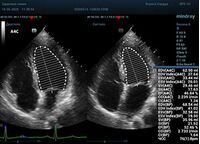

Что могут предложить современные приборы? Приборы нашего времени являются мощными вычислительными машинами, способными обрабатывать полученную информацию даже без помощи человека. Система автоматического вычисления фракции выброса – AUTO EF на приборах серии Resona компании Mindray сделает все за вас. За пару секунд прибор сам отыщет нужную фазу сердечного цикла и произведёт измерение и расчеты, а также покажет график изменения объема в сердечном цикле. От Вас требуется только получить качественное 4С и 2С сечение. Впрочем, прибор всегда оставляет возможность коррекции, если доктор имеет свое мнение на расположение точек планиметрии или момента измерения по ЭКГ каналу.

С появлением В режима реализовалась возможность визуализации всех сегментов миокарда из парастернальных и апикальных сечений. Метод Teicholtz в широкой практике сменился методом дисков. Метод дисков, или метод Simpson, позволяет разбить левый желудочек на 20 дисков, с расчетом объема каждого из них. Используя 2 перпендикулярных сечения, апикальные двух и четырех камерное, мы приближаемся к значению реального объема левого желудочка. Исследователь обводит интерфейс эндокард – кровь в фазу диастолы и фазу систолы. Линия простирается от кольца митрального клапана и до кольца митрального клапана, четко разграничивая объем желудочка от предсердия. Для достоверного изменения необходимо использовать ЭКГ канал.

Обводить вручную эти линии занимало много времени, однако результат того стоил. Следующим шагом стало появление Spline технологии, позволяющее расставлять точки и автоматически их соединять. Такой способ планиметрии контура эндокарда значительно сократил время измерения.